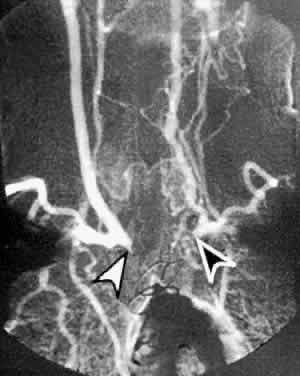

CAROTID ANGIOGRAPHY

Carotid angiography is performed by selective common carotid arterial injection of a radiopaque contrast dye via transfemoral catheterization. In the traditional technique, the image of the inner luminal silhouette is produced on x-ray emulsion (Fig. 10A and B). More recently, digital images and computerized image enhancement have improved resolution and reduced the amount of contrast dye required.46,47 This method can detect ulcerative lesions, severe stenosis, and formation of mural thrombus. It can also demonstrate collateral circulatory patterns.

Fig. 10. A. Digital subtraction aortogram revealing a 90% atherosclerotic stenosis of the proximal left common carotid artery (black arrowhead) and 80% stenosis of the proximal left subclavian artery (white arrowhead). RSCA, right subclavian artery; RCCA, right common carotid artery; RVA, right vertebral artery; LCCA, left common carotid artery; LSCA, left subclavian artery. B. Digital subtraction angiogram with a right common carotid injection from the same patient. There is complete occlusion of the right internal carotid artery due to atherosclerosis (white arrowhead). The right external carotid artery (RECA) and the right common carotid artery (RCCA) fill normally.

Ophthalmic symptoms, due to ocular hypoperfusion from occlusion of the carotid artery, are seen in 15% of cases.59 These ophthalmic changes may be identical to those of ocular ischemic syndrome caused by carotid atherosclerotic disease (see Figs. 5 and 6).60,61 Arteriography of the aortic arch region, showing smooth-walled areas of stenosis and dilation, is usually necessary to confirm the diagnosis (Fig. 11). Collateral circulation, due to the chronicity of the stenosis, is usually prominent.

Fig. 11. Digital subtraction thoracic angiogram of the aortic arch and its major branches in the same patient with Takayasu's arteritis as shown in Figures 5 and 6. The right common carotid artery shows nearly complete occlusion (white arrowhead). The left common carotid artery shows complete occlusion with extensive collateral flow (black arrowhead). (Courtesy Travis A. Meredith, MD, St. Louis MO)